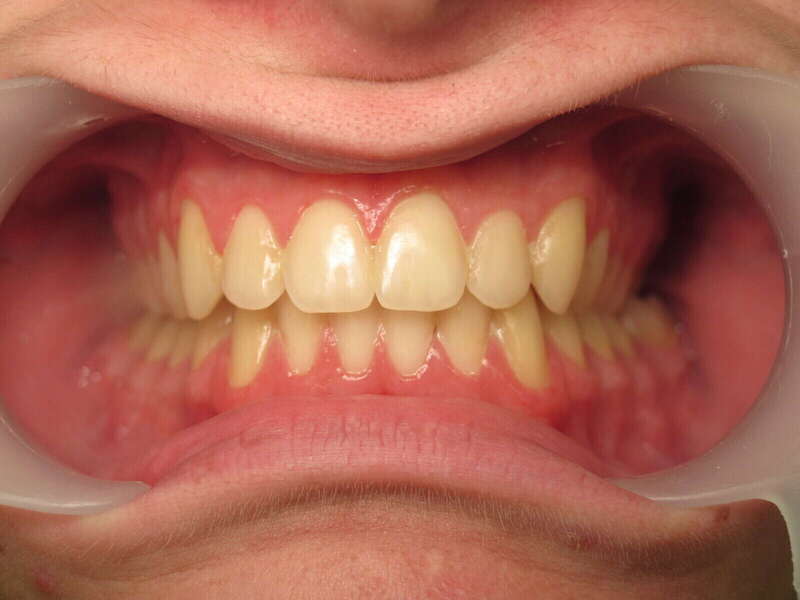

Cas n°1 traité par aligneurs (interception) - enfant

Ce cas d’interception chez un enfant de 8 ans démontre l'efficacité des aligneurs pour corriger des troubles fonctionnels précoces. Le diagnostic présentait des inversions d'articulé provoquant une déviation de la mandibule vers la gauche et un décalage des milieux.

Grâce à une coopération exemplaire et un traitement totalement indolore, l'expansion de l'arcade a permis de recentrer la mâchoire. Cette intervention a littéralement remis la croissance sur les rails, neutralisant le risque d'asymétrie faciale squelettique.

• Correction fonctionnelle : Recentrage immédiat de la mandibule et des milieux inter-incisifs.

• Prévention : Création d'un environnement favorable pour les dents définitives à venir.

• Bien-être : Approche douce respectant le confort de l'enfant.

C'est une étape fondamentale qui simplifie l'avenir orthodontique du patient tout en garantissant un développement facial harmonieux.